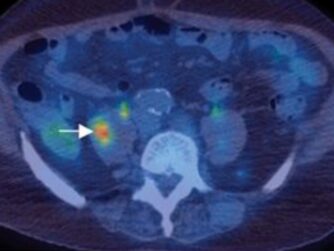

Learn about prostate cancer basics, discussion about early detection such as PSA, and how hormone deprivation therapy affects cancer...